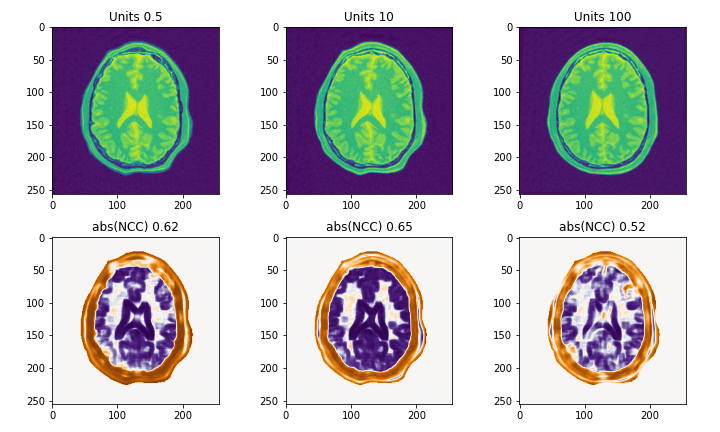

登録結果は以下のようになります.

登録前後のLocal NCC2を計算すると,各ピクセルにおいてNCCの絶対値が向上していることが確認できます.

FinalGridSpacingInPhysicalUnitsの比較

MaximumStepLengthの比較